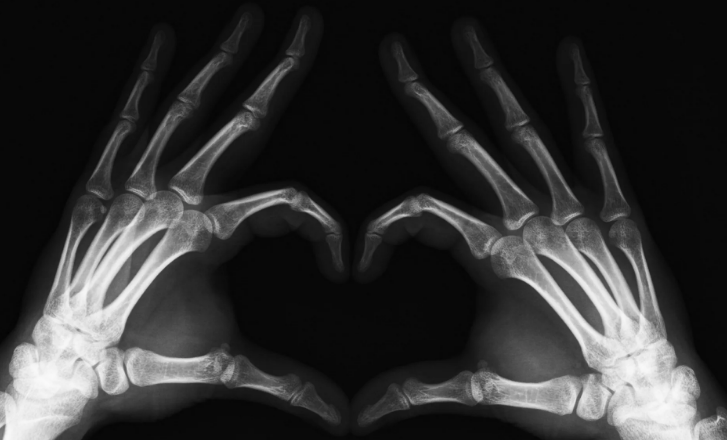

Чисто для интереса сравните с современными снимками.